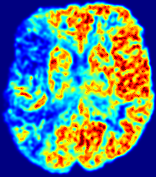

LesionRefer to captionRefer to captionRefer to captionRefer to captionRefer to captionRefer to caption𝐕rgbsubscript𝐕𝑟𝑔𝑏{\bf{V}}_{rgb}Refer to captionRefer to captionRefer to captionRefer to captionRefer to captionRefer to caption𝐕2subscriptnorm𝐕2{\|\bf{V}}\|_{2}Refer to captionRefer to captionRefer to captionRefer to captionRefer to captionRefer to captionRefer to caption3.53.53.52.82.82.82.12.12.11.41.41.40.70.70.70.00.00.0(mm/s)𝑚𝑚𝑠(mm/s)D𝐷DRefer to captionRefer to captionRefer to captionRefer to captionRefer to captionRefer to captionRefer to caption0.0200.0200.0200.0160.0160.0160.0120.0120.0120.0080.0080.0080.0040.0040.0040.0000.0000.000(mm2/s)𝑚superscript𝑚2𝑠(mm^{2}/s)Slice #1Slice #2Slice #3Slice #4Slice #5Slice #6

Figure 4: PIANO feature maps for another patient in the ISLES 2017 training set, where the lesion is located in the right hemisphere. Top row: segmented stroke lesion region (white) on different slices. The corresponding slices for the PIANO feature maps are shown in the following rows.

For a better insight into an estimated velocity field 𝐕𝐕{\bf{V}} and diffusion field 𝐃𝐃{\bf{D}}, we compute the following maps: (1) 𝐕rgbsubscript𝐕𝑟𝑔𝑏{\bf{V}}_{rgb}: Color-coded orientation map of 𝐕=(Vx,Vy,Vz)T𝐕superscriptsuperscript𝑉𝑥superscript𝑉𝑦superscript𝑉𝑧𝑇{\bf{V}}=(V^{x},V^{y},V^{z})^{T}, obtained by normalizing 𝐕𝐕{\bf{V}} to unit length and mapping its 3 components to red, green, blue respectively; (2) 𝐕2subscriptnorm𝐕2\|{\bf{V}}\|_{2}: 222 norm of 𝐕𝐕{\bf{V}}; (3) D𝐷D: scalar field in Eq. 5.

Fig. 3 and Fig. 4 show the PIANO feature maps estimated from two ISLES 2017 patients: all are highly consistent with the lesion in both cases. Details of the blood flow trajectories are revealed in 𝐕rgbsubscript𝐕𝑟𝑔𝑏{\bf{V}}_{rgb} by the ridged patterns and the sharp changes of colors in the unaffected (right) hemisphere, while the flat patterns appearing within the lesion provide little directional information about the velocity and indicate low velocity magnitudes. Velocity magnitudes are more directly visualized via 𝐕2subscriptnorm𝐕2\|{\bf{V}}\|_{2}, from which one can easily locate the lesion where 𝐕2subscriptnorm𝐕2\|{\bf{V}}\|_{2} is low. D𝐷D also indicates lower diffusion values in the lesion, though with less contrast potentially due to the fact that it captures the accumulated effect of CA diffusion at the voxel-level.